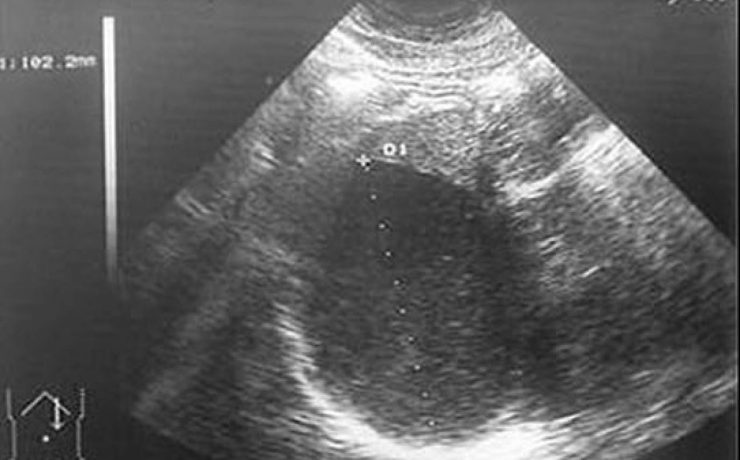

La equinococosis alveolar es causado por el metacestodo Equinococcus multilocularis, en los humanos proliferan en el hígado, induciendo un crecimiento lento progresivo semejante a un tumor. La infección ocurre en todos los continentes, cursa como una infección crónica con estado latente e incluso más de un tercio con detectados incidentalmente,